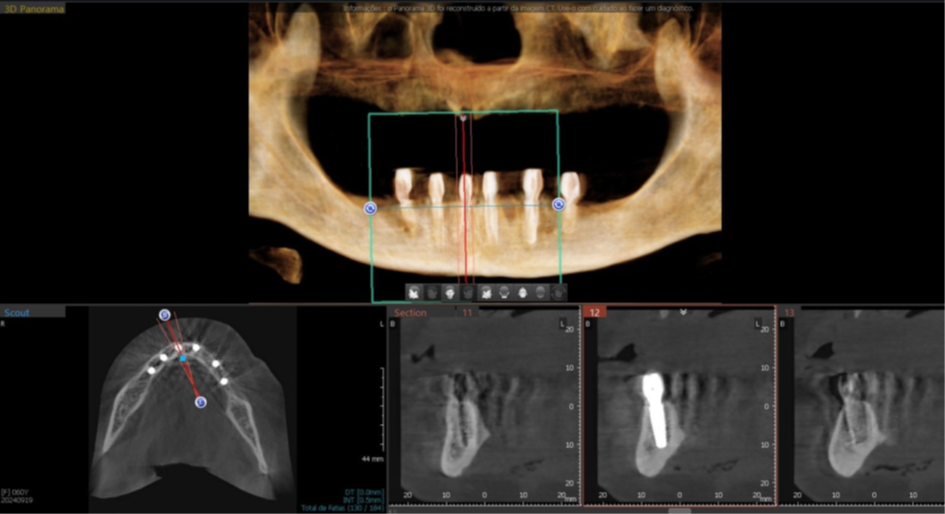

Foram planejados seis implantes nas seguintes medidas: elemento 31: 3.5x11mm; elemento 33: 3.5x11mm; elemento 35: 3.5x7mm; elemento 41: 3.5x11m; elemento 43: 3.5x11mm; elemento 45: 3.5x7mm; que foram distribuídos ao longo da mandíbula. O planejamento virtual do guia cirúrgico foi realizado em parceria com a empresa TechnoGuide, sendo posteriormente validado e aprovado para a confecção do guia definitivo.

Figura 11 – Planejamento digital do implante 41.

Figura 12 – Planejamento digital do implante 43.

Figura 13 – Planejamento digital do implante 45.

Figura 18 – Corte tomográfico implante 45.

Figura 19 – Corte tomográfico implante 43.

Figura 20 – Corte tomográfico implante 41.

Figura 21 – Corte tomográfico implante 31.

Figura 22 – Corte tomográfico implante 33.

Figura 23 – Corte tomográfico implante 35.